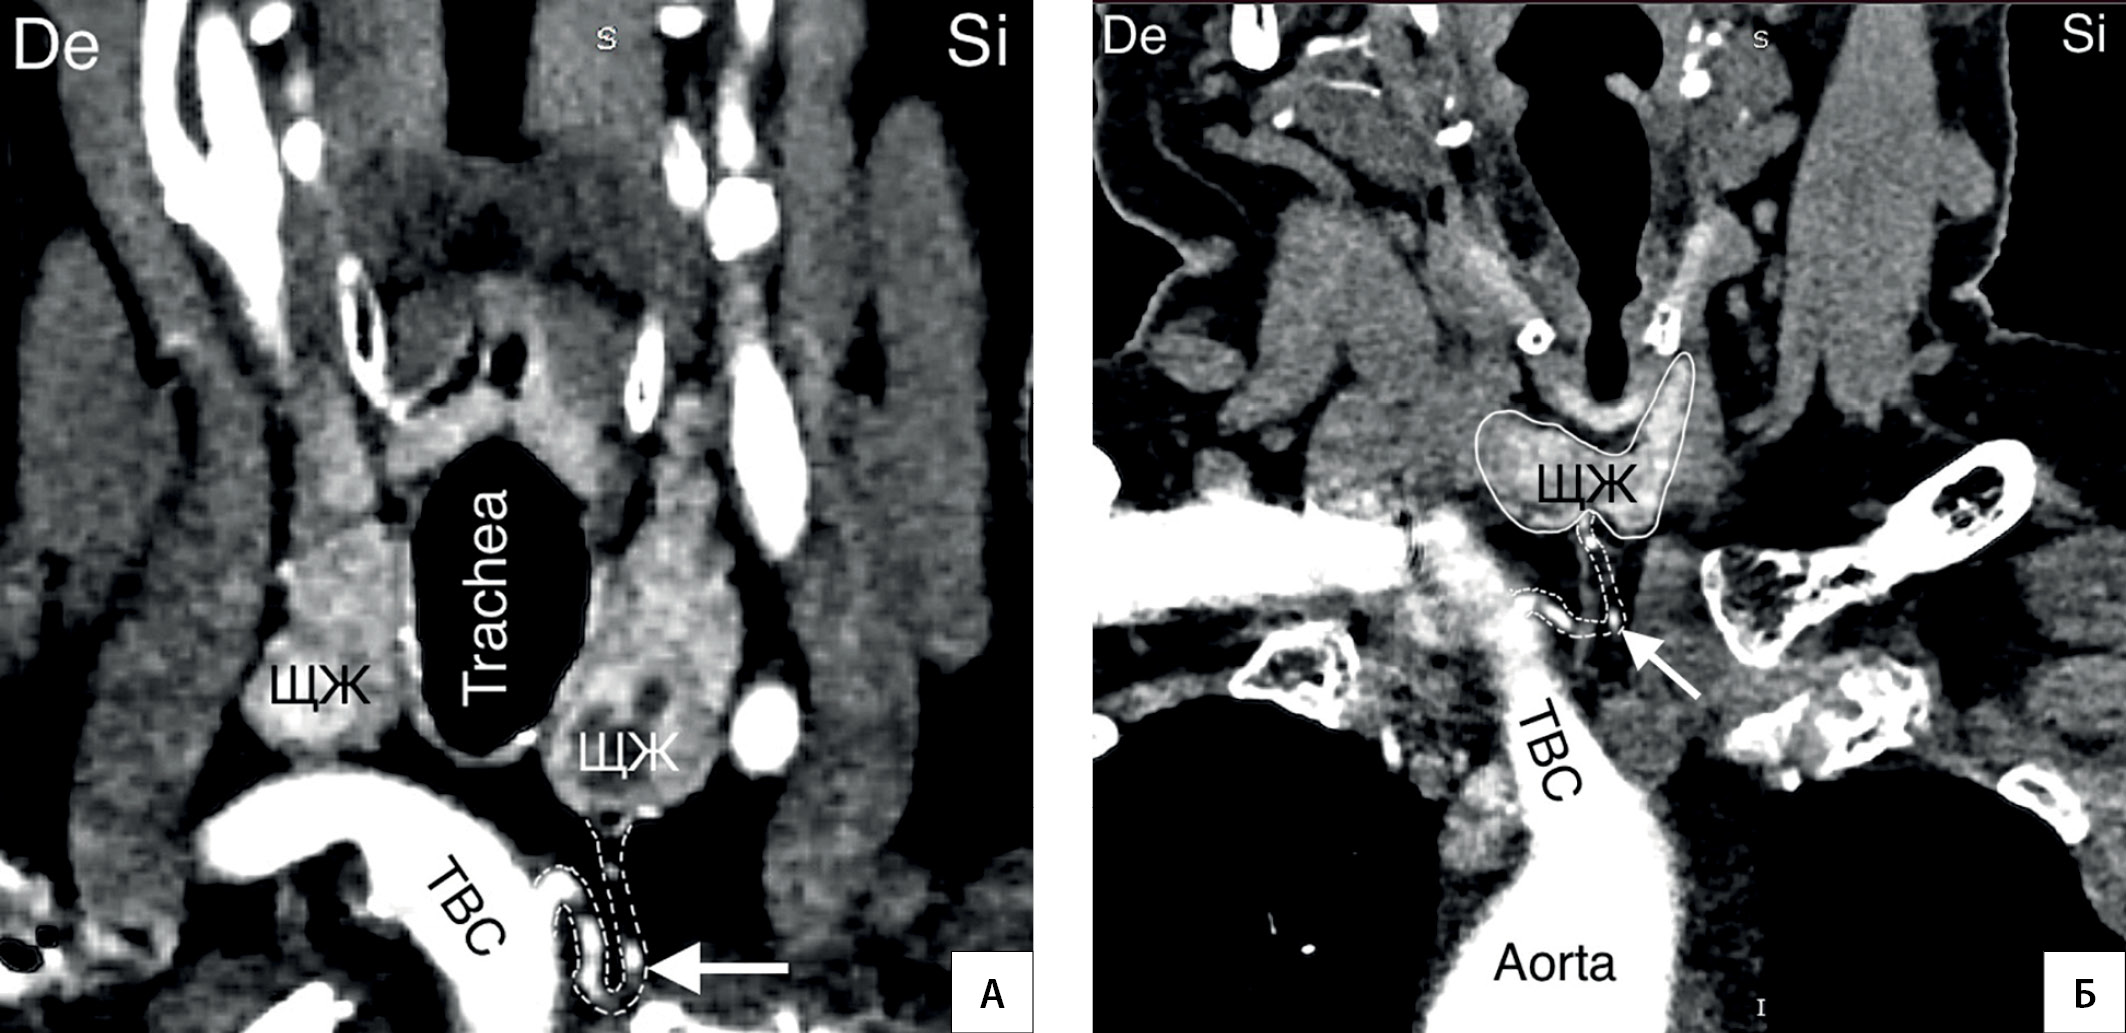

13. Рисунок 13. Непарная щитовидная артерия (указана стрелкой). А, Б — КТ-ангиография (фронтальный срез). TBC — truncus brachiocephalicus; De — dextra; Si — sinistra. | |